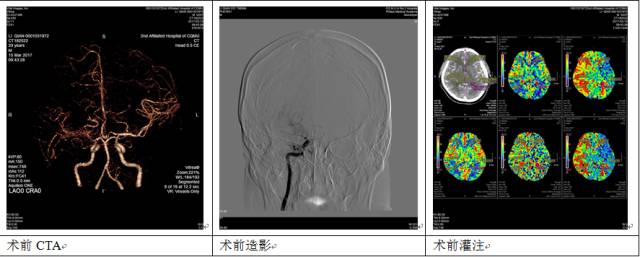

检查结果提示李先生的右侧颈内动脉远端主干血管缺失、颅底血管异常增生,考虑烟雾病,而且灌注像提示右侧大脑半球缺血灌注。

李先生拿着报告单来到了神经外科。蒋永祥主治医师仔细查看了CTA之后,对照着影像资料为李先生详细解释了烟雾病。

半年后,李先生来医院复查了,术后李先生嗜睡、易疲乏的症状明显好转了,完善了脑卒中一站式检查,桥血管通畅,缺血灌注也得到了改善。